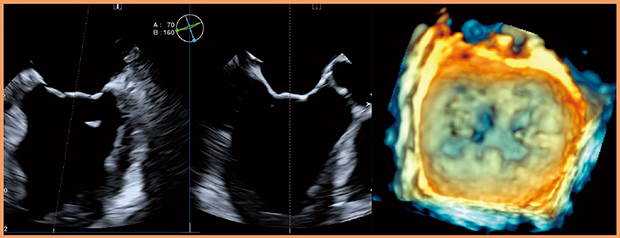

PEI-512VXは,マトリックスアレイ技術を採用し,短時間で高解像度のボリュームデータを取得可能な3D経食道プローブである(図3)。挿入性に優れた先端部形状と,把持しやすい操作部形状が特長である。また,X線が透ける素材を使用しているので,治療用のデバイスとプローブの先端が重なったとしても,ストレスなく手技を実施することが可能である(図4)。

図3 PEI-512VXによる僧帽弁のマルチプレーン像および3D像

(画像ご提供:聖マリアンナ医科大学・出雲昌樹先生)